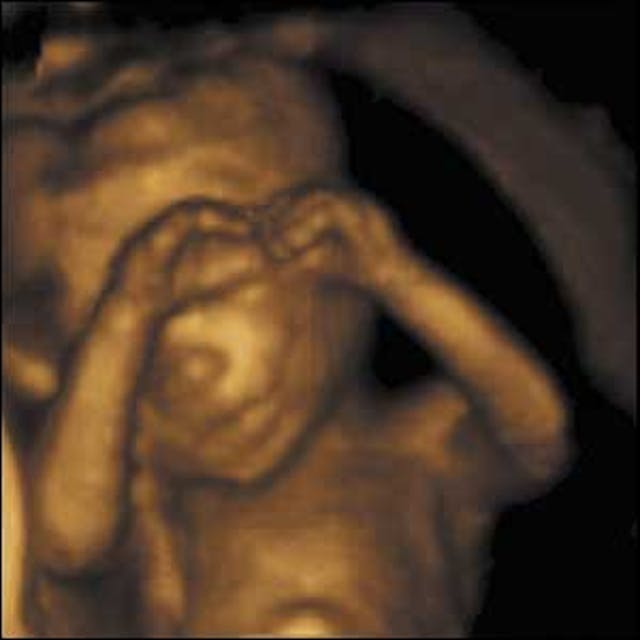

Seeing her child on the ultrasound screen, and gaining a better understanding of the growing life she was carrying during her initial visit, Hillary had been even more impressed with the genuine compassion the staff showed to her at the appointment.

Looking back, Hillary recognizes how much of a difference it made to see her child on screen.

“Many of our clients don’t realize the tiny miracle of life growing inside of them until they see the baby’s picture on an ultrasound,” Carol Dodds, executive director of A Woman’s Friend, said. “Once they see the heartbeat, they know without a doubt that this is not a blob of tissue, but rather a little human being relying on them for sustenance and protection, that the decision they make will save or end a life.”